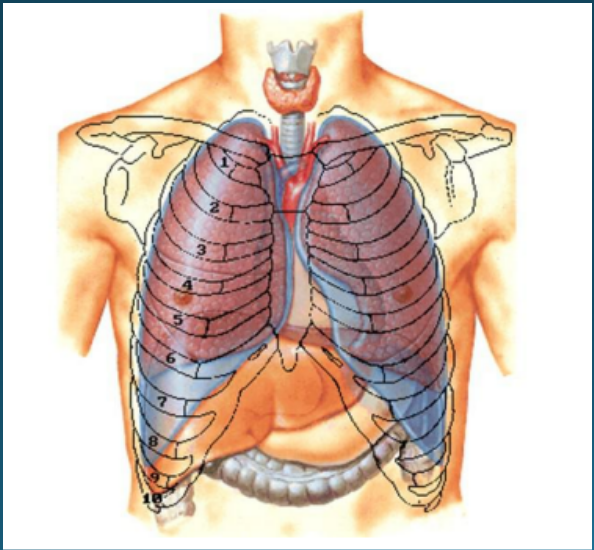

A compreensão da anatomia torácica é fundamental para a interpretação adequada das imagens de TC.

Órgãos principais da respiração, divididos em lobos (3 no direito, 2 no esquerdo)

Via aérea principal que se bifurca nos brônquios principais

Região de entrada e saída de estruturas vasculares e brônquios

Espaço entre os pulmões contendo coração, grandes vasos, esôfago e traqueia

Visão geral da anatomia torácica (Fonte: Wikimedia Commons)